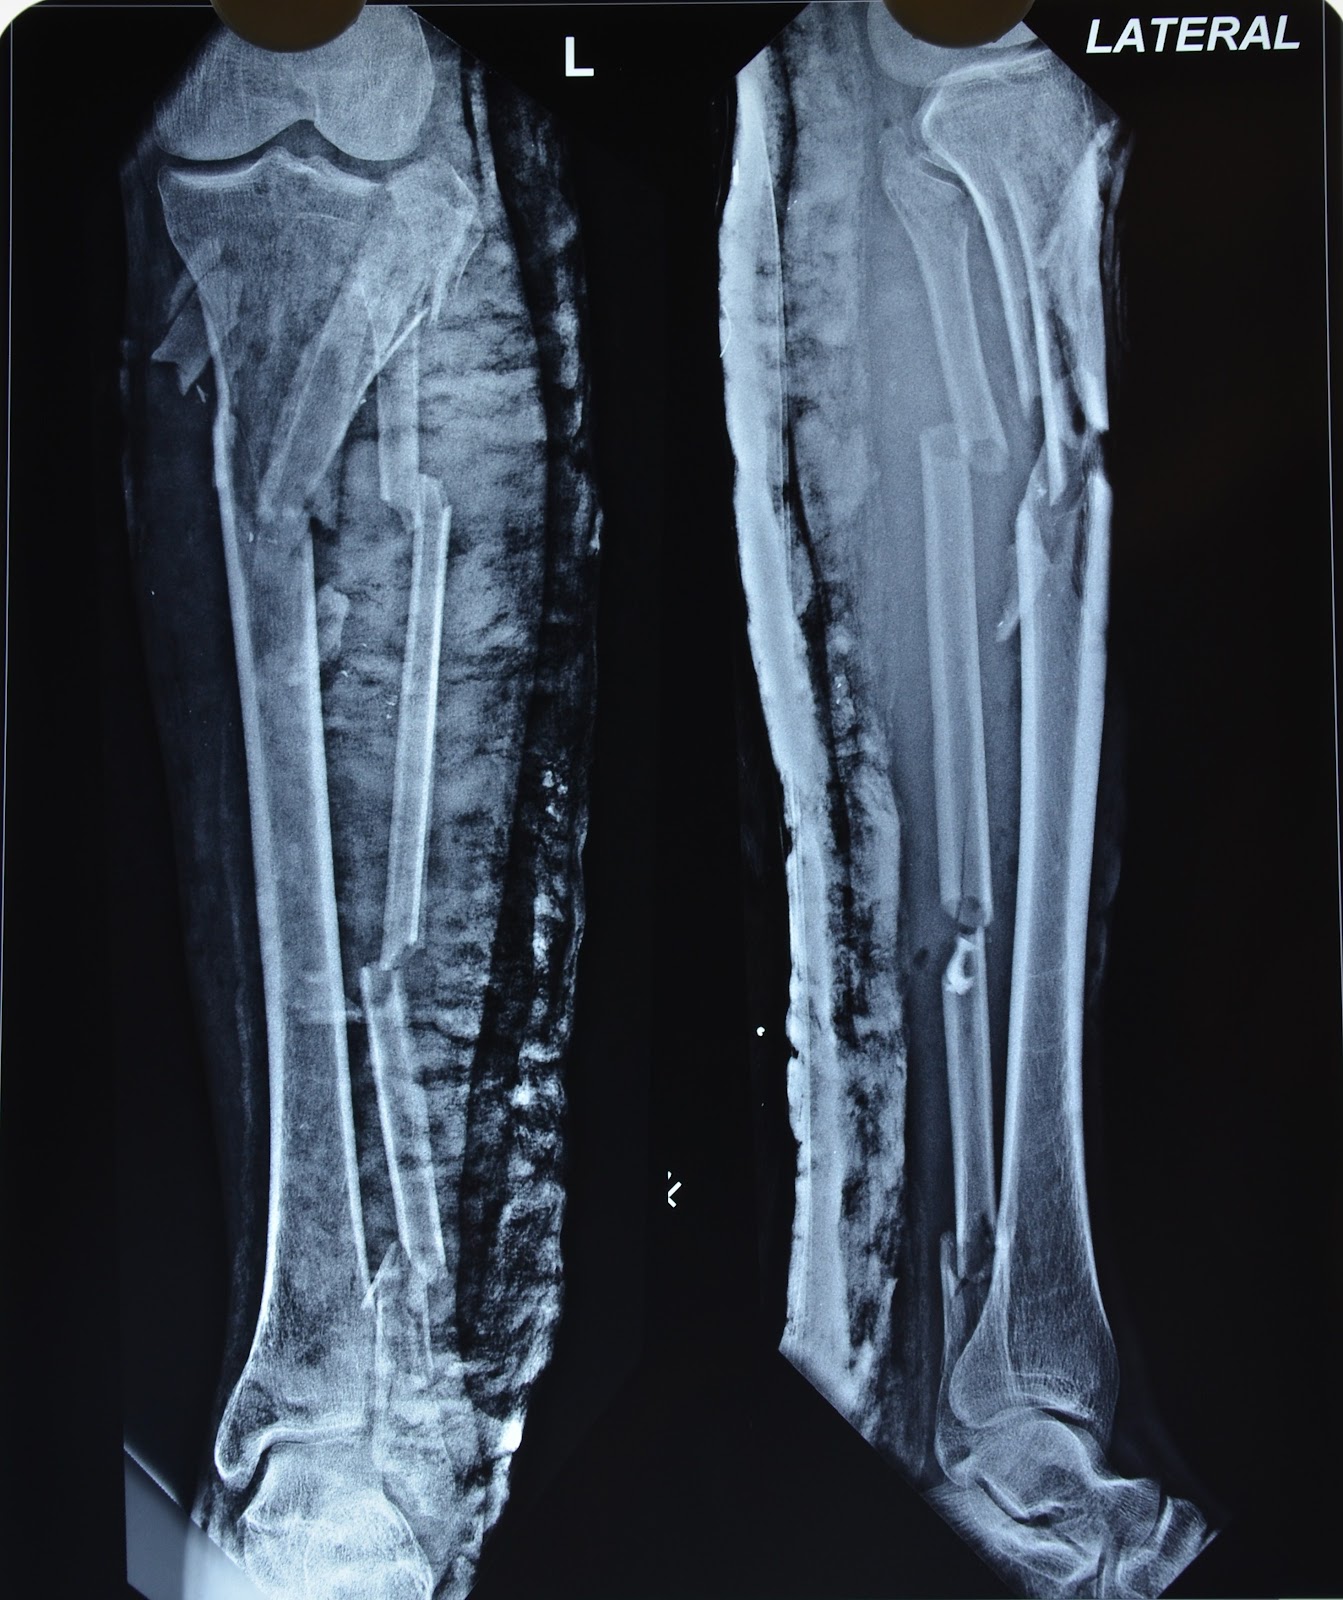

MAJOR CRUSH INJURY LEG AND FOOT NON SALVAGEABLE CRUSH INJURY FOOT Crushing Injury In Foot crush injuries demand immediate attention! These wounds are usually very serious, involving. a foot crush injury is a severe type of broken foot condition. crush injuries of the foot and ankle may range in severity from simple soft tissue contusions with no underlying bony. foot crush injuries are more severe than regular foot fractures. a. Crushing Injury In Foot.

MAJOR CRUSH INJURY LEG WE TRIED BUT LATER DECIDED NOT TO SALVAGE Crushing Injury In Foot crush injuries demand immediate attention! In this injury, the foot is compressed between two hard surfaces,. They occur as a result of direct. These wounds are usually very serious, involving. foot compartment syndrome is a devastating lower extremity condition where the osseofascial compartment pressure rises to a level. foot crush injuries are more severe than regular foot. Crushing Injury In Foot.